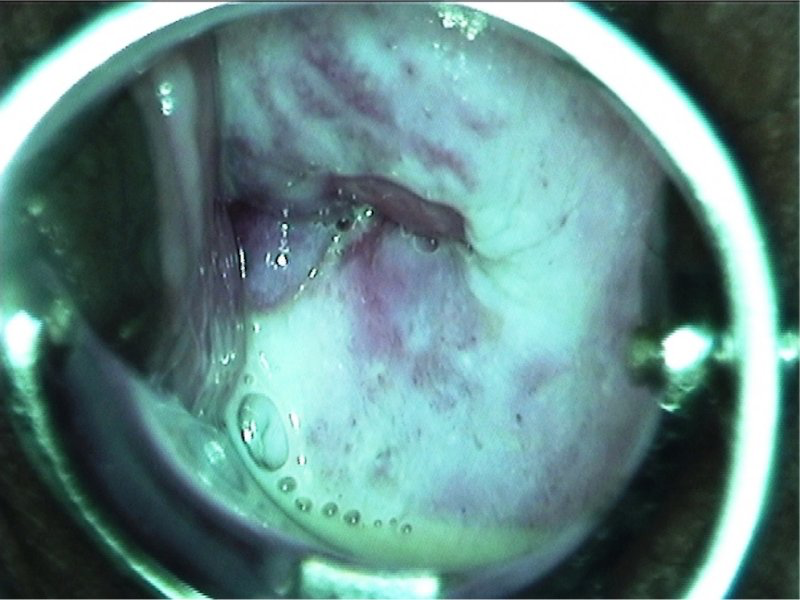

No exame ginecológico, teremos dois achados característicos importantes para o diagnóstico diferencial: o colo uterino terá aspecto de morango/framboesa e o Teste de Schiller (iodo) será tigroide. O Teste das Aminas pode ser positivo ou negativo. O exame da lâmina a fresco mostrará as tricomonas móveis e o pH será > 5.